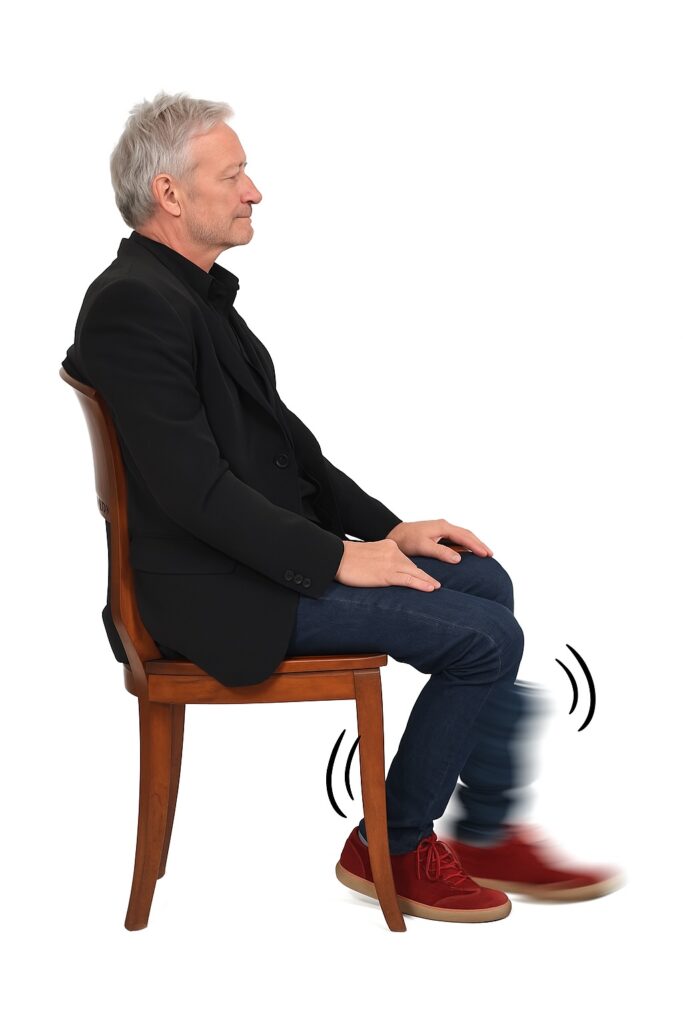

6. Tremor ortostático

É um tipo de tremor pouco conhecido, mas que pode causar grande desconforto.

O tremor ortostático aparece somente quando a pessoa está em pé, parado. Ele provoca uma sensação de instabilidade, como se as pernas não sustentassem o corpo. Algumas pessoas descrevem como se estivessem “flutuando”, “vibrando por dentro” ou “balançando”.

Esse tremor some ao sentar ou ao começar a andar, o que o diferencia de outros tipos.